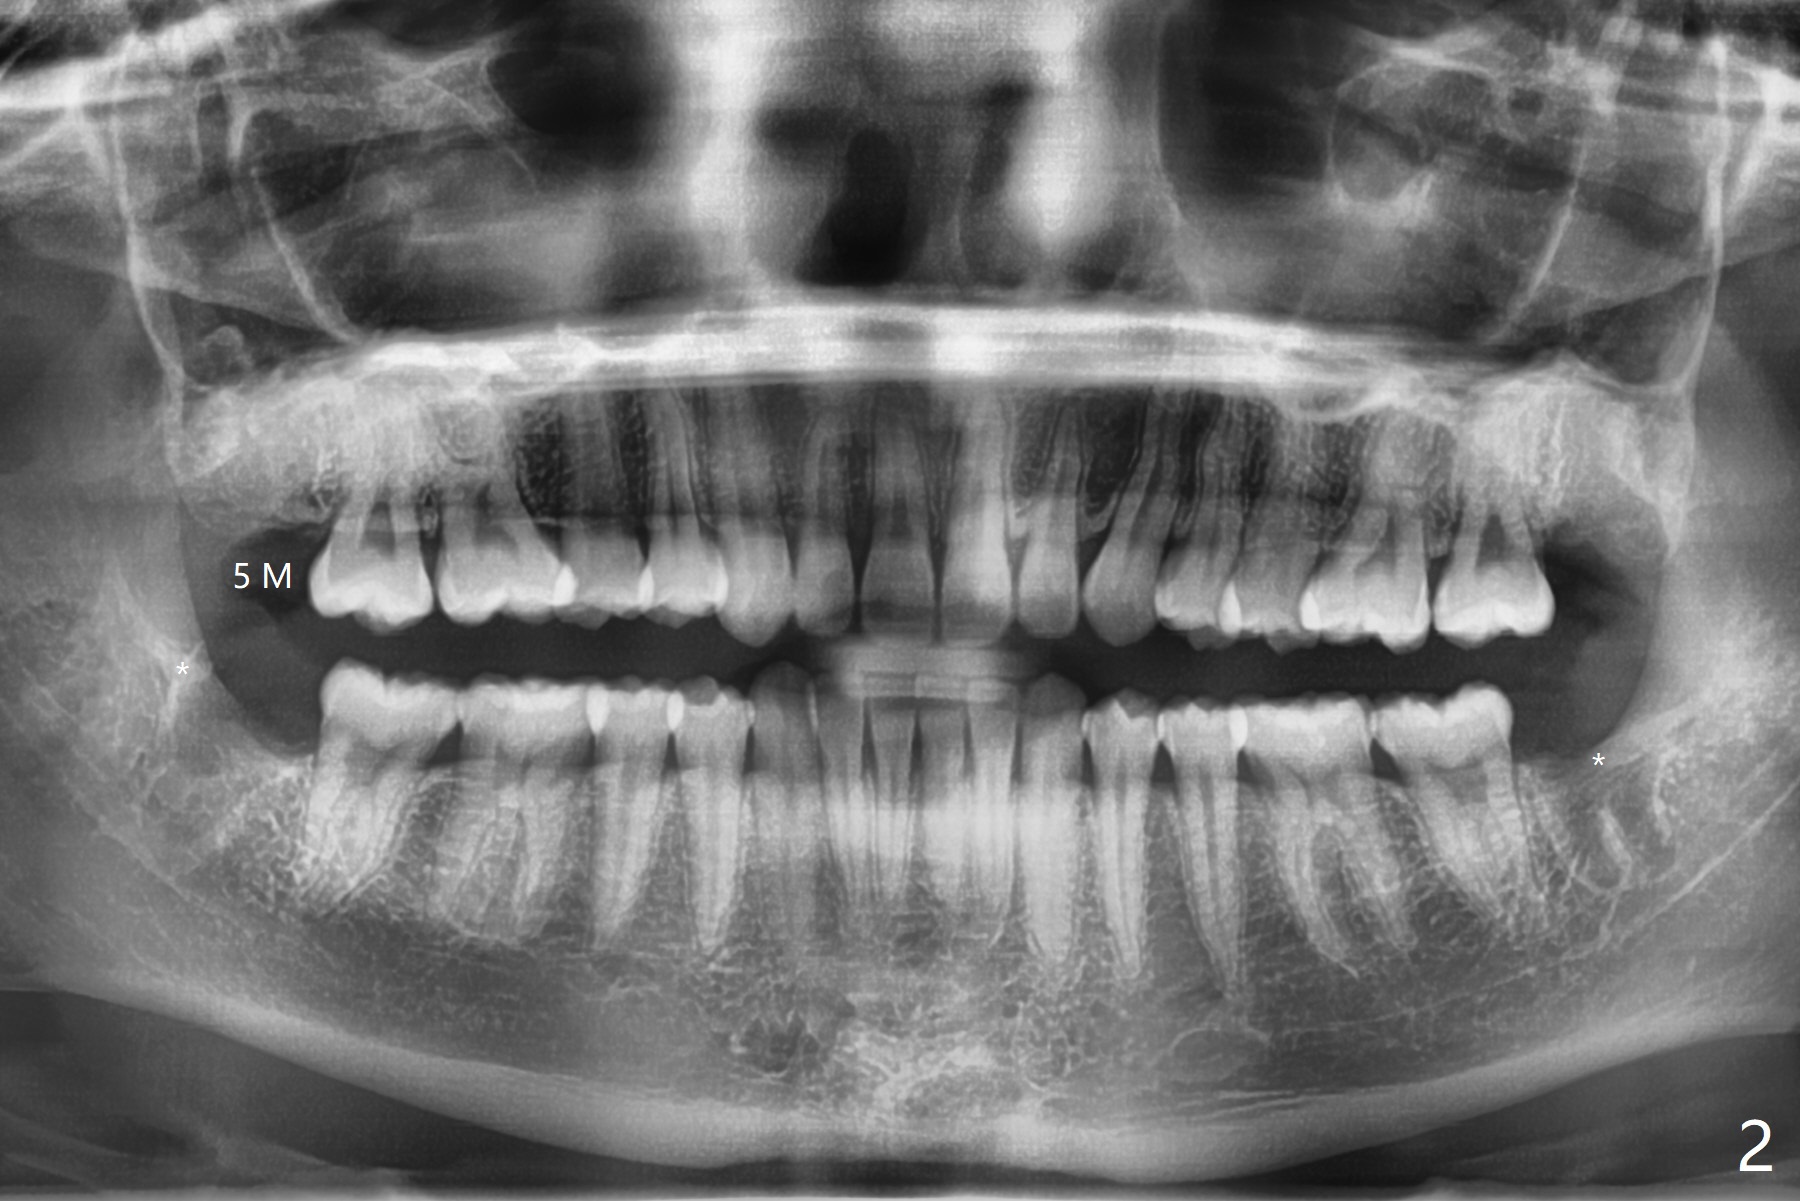

18岁女5个月前拔除右上8时疼痛明显(图一(1-2年前拍摄)),要求多打麻药拔除其余智齿。右下拔除需要切开,去骨,但是不需要分根,近中面旋转接近颊侧;左下基本萌出,拔除不需要切口,两个牙槽窝都放置胶原塞,左侧在没有减张下用4-0 Chromic Gut suture缝合,伤口基本关闭(但愿没有裂开)。右侧外斜嵴中止于远中牙槽嵴(与去骨有关?),而左侧跨越远中牙槽窝(图二:*)。术后4-5天右侧出现干槽症,局部冲洗,几天后症状消失(PRF似乎重要),而左侧伤口没有裂开。